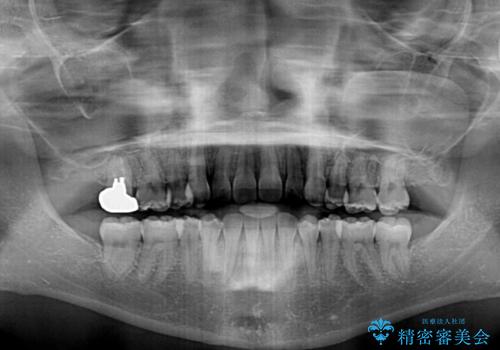

本人は気づいていませんでしたが、下顎前歯が2本欠損しており、上下の歯列がアンバランスとなりデコボコになっていました。

上下のバランスを取るため、上顎左右第一小臼歯2本を抜歯し、ワイヤー矯正を行うこととしました。

抜歯矯正を行ったことで、デコボコが改善されただけでなく、口元も下がったことで口が閉じやすくなりました。